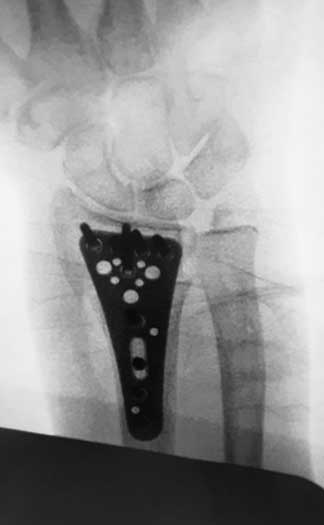

Durante mi entrenamiento en mi segundo fellow en cirugía articular y lesiones deportivas, tuve la oportunidad de hacer una rotación en el hospital CEMA by FIFA (Centro de Excelencia Médica en Altura) en Pachuca Hidalgo, donde brindé atención médica y quirúrgica en las instalaciones de la Universidad a pacientes deportistas profesionales y de alto rendimiento, miembros del equipo de fútbol “Tuzos de Pachuca”.

Galería